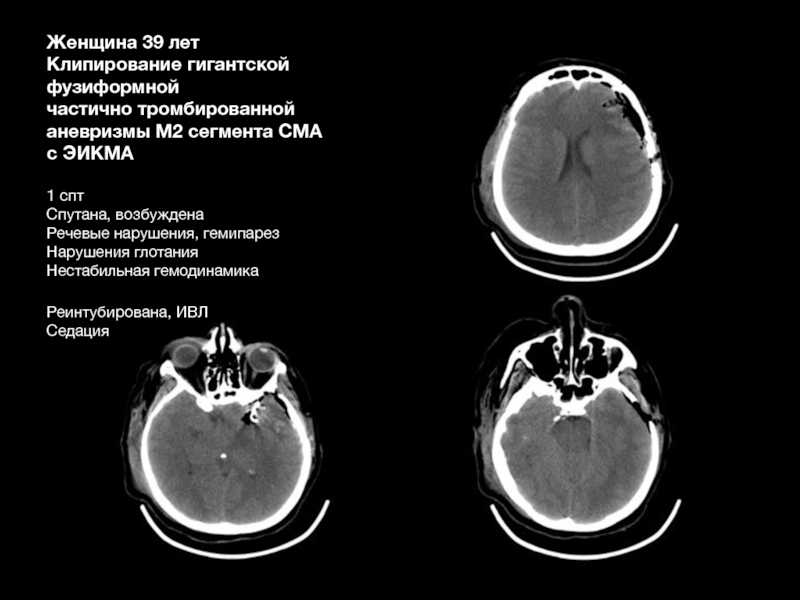

Слайд 66Женщина 39 лет

Клипирование гигантской

фузиформной

частично тромбированной

аневризмы М2 сегмента

СМА

с ЭИКМА

1 спт

Спутана, возбуждена

Речевые нарушения, гемипарез

Нарушения глотания

Нестабильная гемодинамика

Реинтубирована, ИВЛ

Седация

Женщина 39 летКлипирование гигантской фузиформной частично тромбированной аневризмы М2 сегмента СМА с ЭИКМА 1 сптСпутана, возбужденаРечевые нарушения,